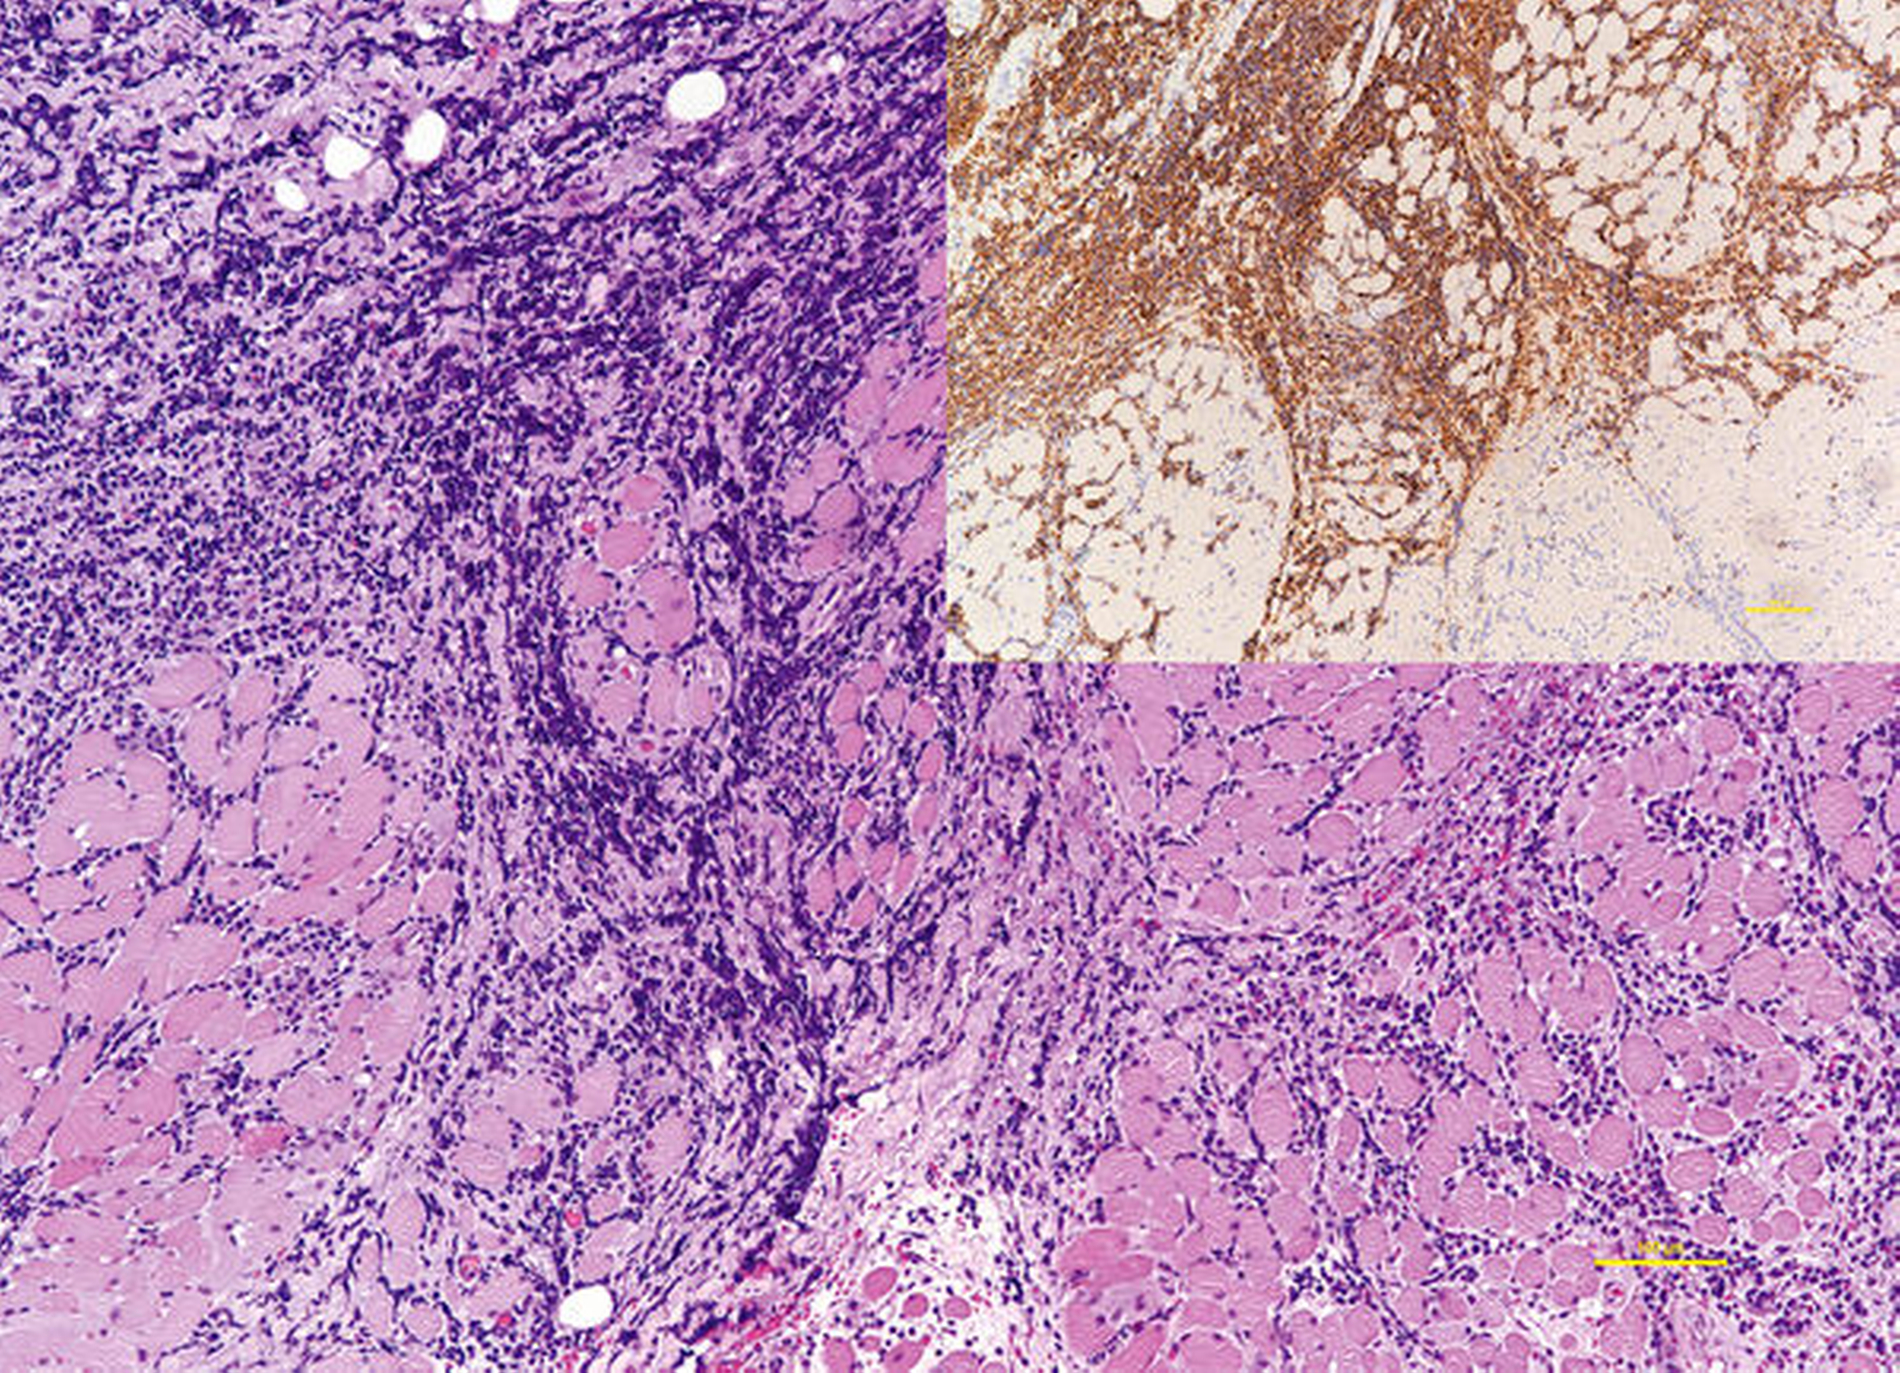

In der CT-Untersuchung mit Kontrastmittel zeigte sich eine ausgedehnte Raumforderung der rechten Wange, die keinerlei klare Infiltration oder Destruktion der anatomischen Nachbarstrukturen aufwies (Abbildung 3). Zur weiteren Diagnostik erfolgte in Lokalanästhesie von intraoral eine Probenentnahme. Im histologischen Präparat zeigte sich ein diffuses, sich ausbreitendes Infiltrat aus mittelgroßen, runden Blasten im fibrösen Weichgewebe und Fett ohne eine erhaltene Lymphknotenstruktur.

Es wurde die Diagnose eines hochmalignen, hochproliferativen Non-Hodgkin-Lymphoms (NHL) der B-Zellreihe, in erster Linie ein diffuses, großzelliges B-Zell-NHL (diffuse large B-cell lymphoma, DLBCL) gestellt. Speziell lag ein proliferationsaktives DLBCL, NOS (not otherwise specified) vom aktivierten B-Zell-Typ (activated B-cell type, ABC) mit einer MYC-Translokation vor (Abbildung 4). Das im Rahmen des komplettierenden Stagings durchgeführte FDG PET-CT zeigte einen intensiv verstärkten Glucosemetabolismus der vorbekannten Raumforderung in der rechten Wange (Abbildung 5). Insgesamt ergab sich kein Nachweis auffällig Glucosemetabolismus-gesteigerter Lymphknoten im gesamten Untersuchungsvolumen. Die knöchernen Strukturen zeigten keine suspekten osteoproliferativen oder osteodestruktiven Prozesse. Ausgehend von einem isolierten Befall der Weichteile rechts buccal wurde das NHL nach Abschluss des Stagings als Stadium I nach der Ann-Arbor-Klassifikation eingestuft.